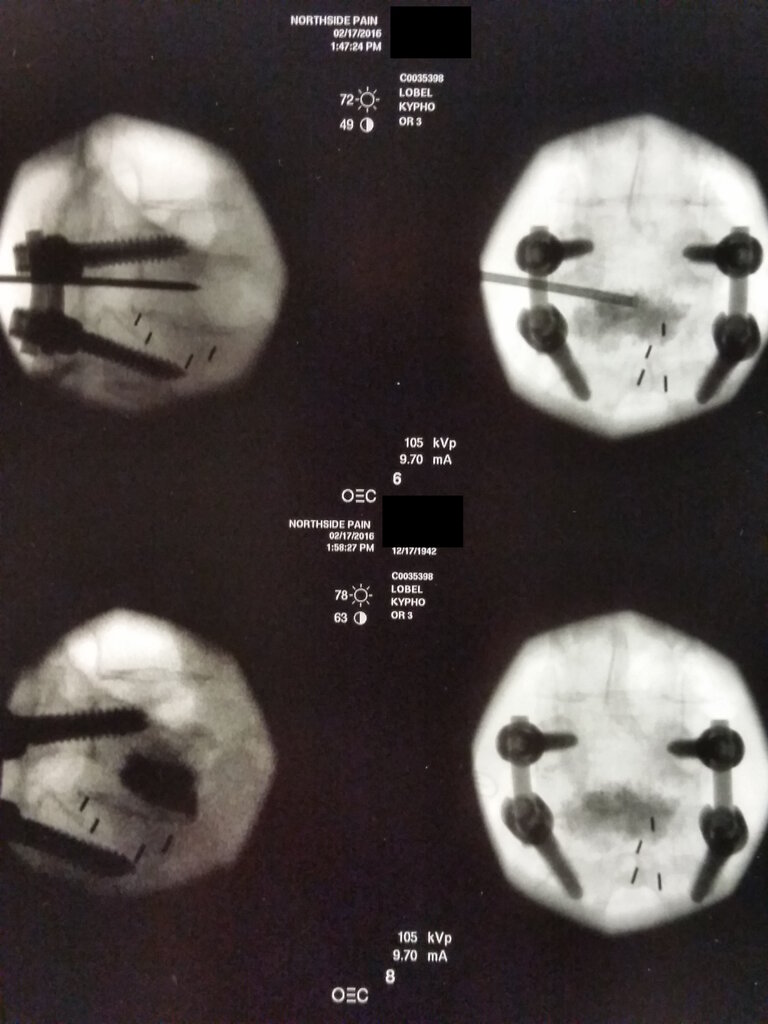

83 y/o F with new L5 compression fracture from 2 months back (30% superior endplate compression) with fracture lines that extend into the bilateral pedicles, L>R.

I want to fix this thing, but she also has history of L4-S1 posterior fusion with bone graft (fusion done in 1975) going right over the pedicle shadow. Hard to make out any definable anatomy needed on left, but I do see my landmarks on right.